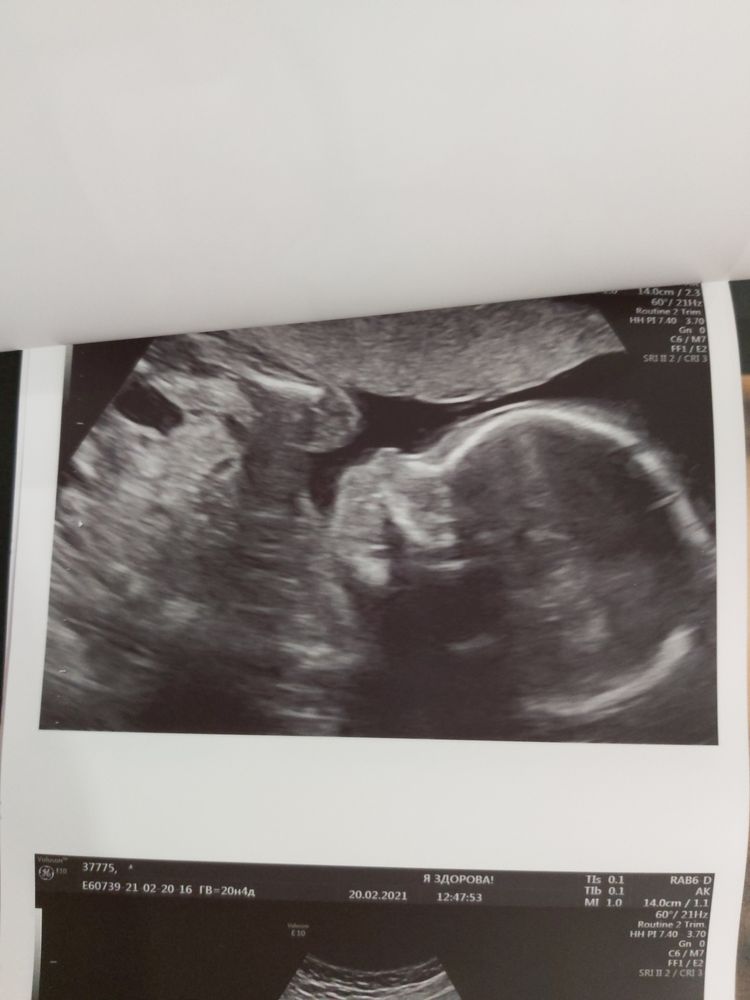

Немножечко фото нашей маленькой врединки🥰